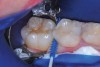

The authors' protocol for insertion of SDF-coated soft dental picks involves isolating the teeth with cotton rolls or other means, flossing the interproximal site to clear food debris and dental plaque, and then inserting a SDF-coated pick (Figure 1 and Figure 2) to saturate the contacting surfaces of the teeth with the fluid. This treatment is painless and requires no anesthetic. The pick should remain in place for at least 60 seconds and can be gently pulled in and out to agitate the fluid for enhanced surface coverage by capillary action. Additional SDF can be wiped on, using a small applicator, above the contact and in the buccal and lingual sluiceways. Excess fluid and any blood elicited may be blotted with a cotton swab. An additional 60-second insertion may be applied in the same way if there is radiographic evidence of a deeper decalcification or caries lesion. With the pick still in place, 5% (or 2.5%) fluoride varnish is painted over the treatment area, and the pick is then withdrawn.

Interproximal insertion of SDF is demonstrated in different patients in Figure 3 through Figure 11. Various diameters and brands of soft dental picks may be used depending on the closeness of the proximal surfaces and ease of insertion; for example, some picks are designed for use in wider spaces between teeth. This protocol also offers versatility. Figure 3, for example, shows the simultaneous use of three thin soft dental picks to saturate proximal surfaces with SDF in a teenaged patient; the treated regions were subsequently covered with fluoride varnish (Figure 4). This patient was initially treated in April 2019 (Figure 5), with an identical re-application 3 months later. As shown in Figure 6, the December 2019 bitewing film revealed good results with the possible exception of the contact regions of the maxillary first and second molars. New SDF application was completed in the December appointment.

Fig 3. Three thin soft dental picks were used simultaneously for SDF proximal surface saturations in a teenaged patient (Fig 3). After 60 seconds, the treated regions were covered with 5% fluoride varnish (Fig 4). A comparison can be seen of pre-SDF-treatment bitewing films (Fig 5) and 8-month post-SDF bitewing films (Fig 6) for the patient shown in Fig 3 and Fig 4. Radiolucencies were similar or improved, except for contact of maxillary first and second molars.

Figure 3